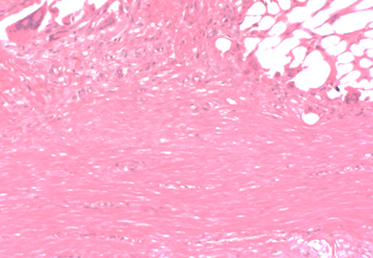

Rapid Cellular Infiltration: The highly porous scaffold provides the ideal environment for cell infiltration and proliferation to form new, functional tissue.

The BioBrace® Implant Filled With New Tissue

Oriented New Tissue Generation: The advanced 3D structure of BioBrace® provides internal channels that naturally guide alignment of new fibers.